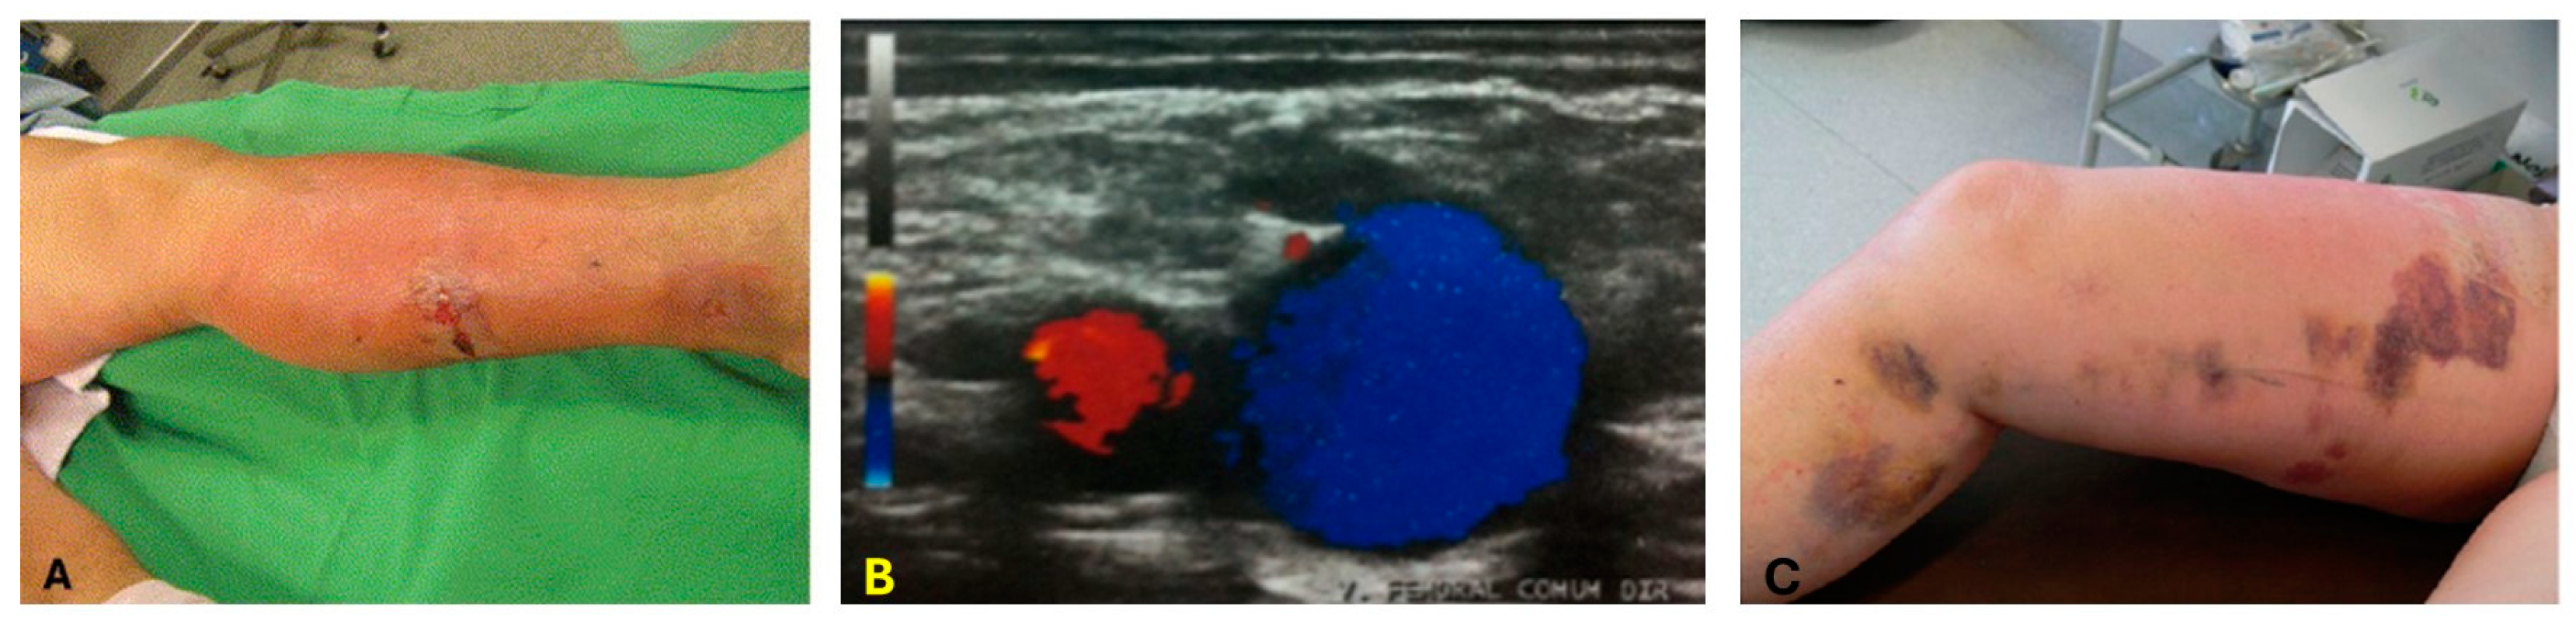

- Yan, Y.; John, S.; Ghalehnovi, M.; Kabbani, L.; Kennedy, N.A.; Mehrmohammadi, M. Photoacoustic Imaging for Image-guided endovenous Laser Ablation procedures. Sci. Rep. 2019, 9, 2933. [Google Scholar] [CrossRef] [PubMed]

- Yan, Y.; John, S.; Shaik, T.; Patel, B.; Lam, M.T.; Kabbani, L.; Mehrmohammadi, M. Photoacoustic-guided endovenous laser ablation: Characterization and in vivo canine study. Photoacoustics 2021, 24, 100298. [Google Scholar] [CrossRef]

- Yan, Y.; John, S.; Ghalehnovi, M.; Kabbani, L.; Kennedy, N.A.; Mehrmohammadi, M. Ultrasound and photoacoustic imaging for enhanced image-guided endovenous laser ablation procedures. In Proceedings of the Medical Imaging 2018: Ultrasonic Imaging and Tomography, Houston, TX, USA, 14–15 February 2018; pp. 184–189. [Google Scholar]